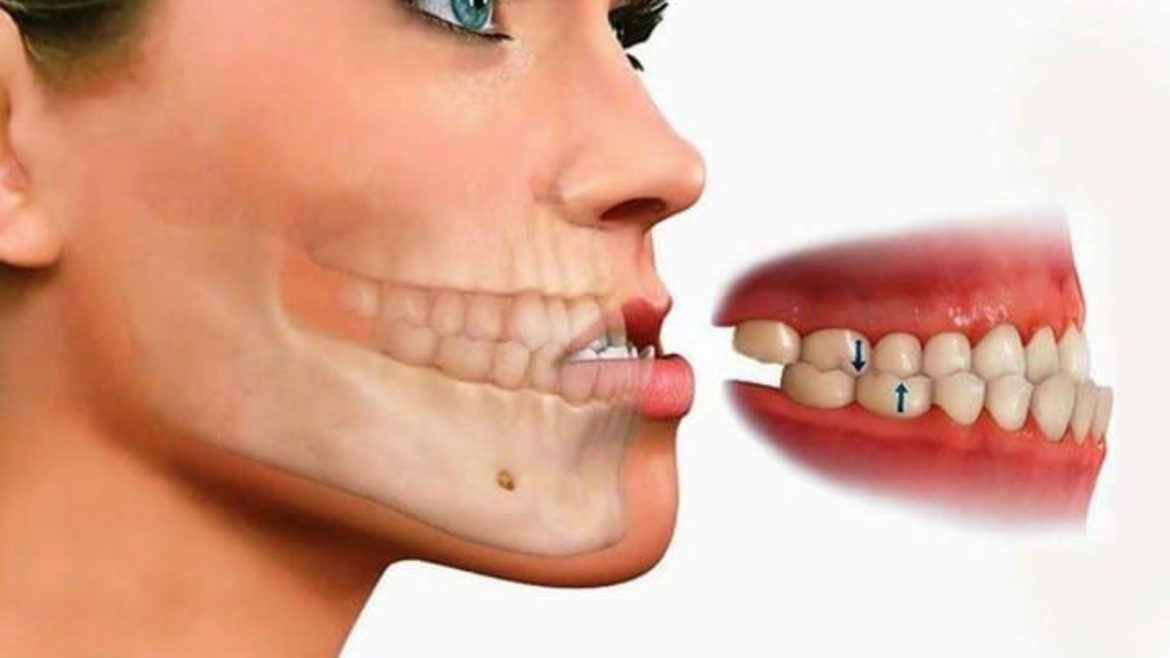

Niềng răng là biện pháp giúp đem lại vẻ đẹp cho con người? Vậy, 19 tuổi niềng răng bao lâu bạn có bao giờ tự hỏi chưa? Có những biện pháp nào giúp rút ngắn thời gian niềng răng? Những …